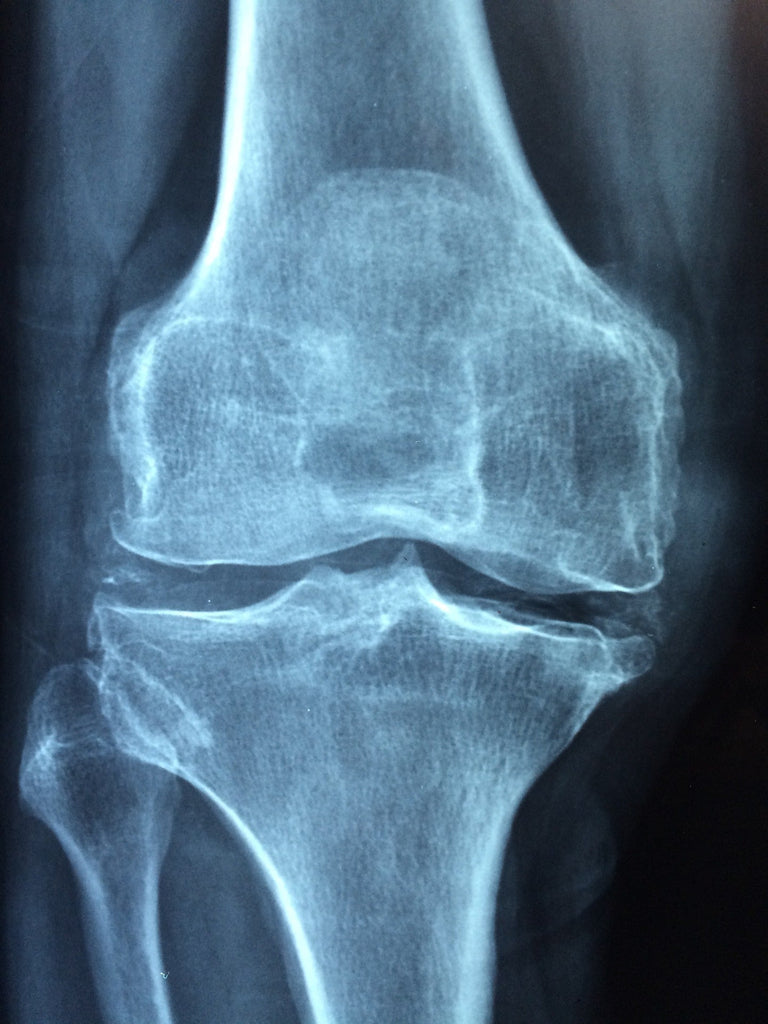

Osteoporosis is a bone disease that occurs when the body loses too much bone, makes too little bone, or both. As a result, bones become weak and may break from a fall or, in serious cases, from sneezing or minor bumps.